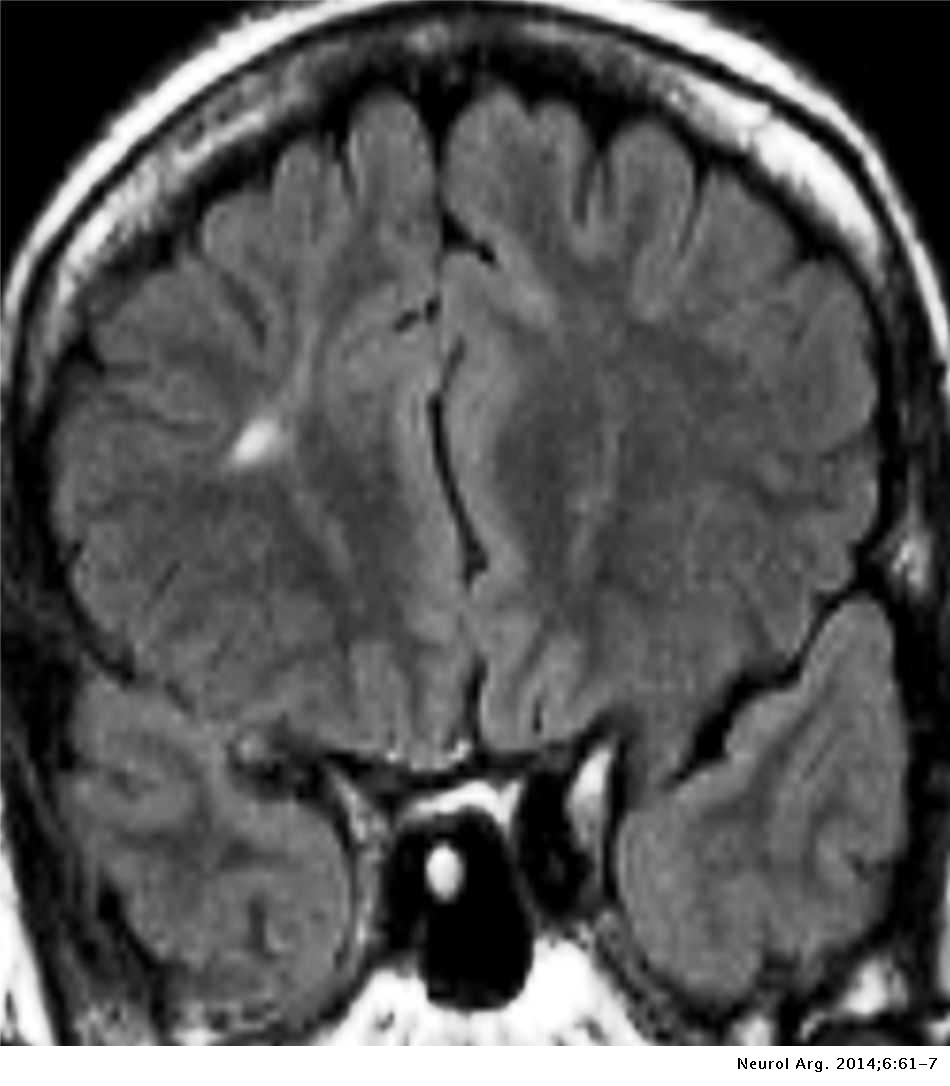

Lista muestra hermosas imágenes de resonancia magnética cerebral normal y anormal dinosenglish.edu.vn para que puedas explorar más en detalle.

resonancia magnética cerebral normal y anormal Pin en NEUROCIENCIAS resonancia magnética de cerebro Resonancia magnética (RM) de cerebro, corte axial ponderado en T2: la … VIDEO Nueva mancha en la Resonancia

Engineer Team : RESONANCIA MAGNETICA Magnetic Resonance Imaging – Clinical Images Hallazgos por resonancia magnética cerebral de nuestro paciente. M, 21 … Imágenes por resonancia magnética anormales como predictoras de mal … Imágenes por resonancia magnética anormales como predictoras de mal … Lesiones en resonancia magnética (RM) del encéfalo y la médula espinal … Pin en Resonancia Magnética del Encéfalo A) Resonancia magnética cerebral (RMC) mostrando infartos en … Caso 1: Edema cerebral visualizado mediante RM. (A) Secuencia T1 plano … Rascacielos dormir pasta tac y resonancia diferencias retrasar … Pin on Apuntes de Enfermería y T.C.A.E Resonancia magnética cerebral secuencia T2, que muestra lesión … Meningitis aguda en la enfermedad de Behçet | Reumatología Clínica Resonancia magnética coronal normal del cerebro Fotografía de stock – Alamy Imágenes de resonancia magnética, la imagen de la cabeza en diferentes … Resonancia magnética cerebral A) protocolo T1 sagital (Caso 1). Se … Resonancia magnética cerebral. Secuencia T1 corte sagital. Atrofia … Resonancia magnética de cerebro, cortes axiales, secuencias T2. Señal … Resonancia magnética de cráneo. A y B) Cortes axiales FLAIR … Resonancia magnética (RM) de cerebro, corte axial ponderado en T2: la … RM cerebral: Interpretación paso a paso | Kenhub Resonancia magnética de cerebro, cortes axiales, secuencias T2. Señal … De Resonancia Magnética De Cerebro Foto de archivo – Imagen de arteria … Top 107+ Imagenes de resonancia cerebral normal – Destinomexico.mx -Imagen por resonancia magnética del cerebro. a) Cortes sagital y axial … resonanCia magnétiCa Cerebral donde se observa hiperintensidad a nivel … MRI (Imagen de resonancia magnética) – Tomografía computarizada de la … Meningioma – NCI Imágenes por resonancia magnética coloreadas del cerebro sano del … Resonancia magnética cerebral en secuencia FLAIR, que muestra lesiones … Contraste resonancia magnetica cerebral – senturinthegreen Relación de los espacios de Virchow-Robin con la enfermedad de … Gliomatosis cerebral – Instituto Nacional del Cáncer Pin en Neurology. Recomendaciones para la utilización e interpretación de los estudios de … Fotografía De La Proyección De Imagen De Resonancia Magnética Del … atmósfera Dirigir Cumplir anatomia resonancia magnetica Desarrollar … Pin en #MEDICINA,#SALUD Resonancia magnética de la nasofaringe De Resonancia Magnética De Cerebro Foto de archivo – Imagen de polilla … Atrofia cortical global de predominio parietal en la Resonancia … Resonancia magnética cerebral | Download Scientific Diagram Neuroblog: Resonancia magnética cerebral en la trombosis crónica de … De Resonancia Magnética De Cerebro Imagen de archivo – Imagen de … ¿Cuáles son los riesgos de la resonancia magnética? – Integra Salud … Resonancia magnética cerebral al decimocuarto día de ingreso: área … Resonancia magnética. Corte axial mostrando área infartada en el … Resonancia magnética cerebral del paciente AV evidenciando lesiones en … -Ressonância magnética de encéfalo mostrando múltiplas imagens … Resonancia magnética cerebral secuencia FLAIR (Fluid Attenuated … Resonancia magnética cerebral con protocolo de epilepsia, en sección … Resonancia magnética cerebral en corte sagital. Se observa una evidente … Resonancia magnética craneal en la que se evidencian lesiones … Logran visualizar el cerebro a detalle más completo tras una resonancia … Así decide el cerebro la severidad de un castigo De Resonancia Magnética De Cerebro, Imagen de archivo – Imagen de … A) Resonancia magnética cerebral; Secuencia Tof: oclusión de arteria … Un estudio asocia la ansiedad con la aparición rápida del Alzheimer IMÁGENES DE 18 F-PR04.MZ PET FUSIONADA CON RESONANCIA MAGNÉTICA … Imágenes por resonancia magnética anormales como predictoras de mal … Tumores de la región pineal – Instituto Nacional del Cáncer Epilepsia: una historia de voces y fantasmas | Neurología Contribución de las imágenes de resonancia magnética por tensor de … Resonancia magnética secuencia T2 plano coronal de quiste epidermoide … Resonancia Magnética Cerebral del paciente: a. Aumento de… | Download … Resonancia magnética cerebral 2022 Síndrome de hemiconvulsión-hemiplejía-epilepsia. Seguimiento de un caso … Enfoque Radiologico: La resonancia magnética permite detectar lesiones … Resonancia magnética craneal T1 con contraste que muestra angiomatosis … guidewiz – Blog Resonancia magnética cerebral, secuencia SWI. Ribete hipointenso en la … resonAnCiA mAgnétiCA de ColumnA Con gAdolinio. Corte sAgitAl en t1 de … SEMANA 12: FUNDAMENTOS DE RESONANCIA MAGNÉTICA NUCLEAR. INDICACIONES Y … DIAGNÓSTICO DE ESCLEROSIS MÚLTIP Magnetic resonance imaging of the brain – Alchetron, the free social … Resonancia magnética de órbitas | Instituto Radiológico Dr. E Castillo Alteración de la marcha en un paciente post-trasplante hepático Resonancia magnética cerebral de un paciente sano (Ay B) y paciente que … Utilidad de la resonancia magnética craneal para el diagnóstico de la … Resonancia Magnética Del Cerebro El Tumor Cerebral Foto de stock y más … De Resonancia Magnética De Cerebro Imagen de archivo – Imagen de … ABDALLA RADIOLOGIA: NEURINOMA ACUSTICO Atrofia cortical global de predominio parietal en la Resonancia … Resonancia Magnética : Producción de la imagen MRI Brain Scan — Stock Photo © Bunyos30 #18724051 Mri (imagen de resonancia magnética) Monitor con imagen de captura de … Tomografía computarizada vs resonancia magnética: diferencia y … Tumores Cerebrales – Unidad de Neurocirugía RGS Resonancia magnética de la columna, sección sagital. Observe los discos … La resonancia magnética, una técnica imprescindible en el diagnóstico … Perfusión Cerebral por Resonancia Magnética | ¿Qué es? ¿Necesita Contraste? Resonancia Magnética Cerebro A: resonancia magnética, T2 coronal preoperatoria; se observa lesión en … Resonancia magnética cerebral — Foto de stock © Bunyos30 #27340623 La resonancia magnética se perfila como detector de mentiras | Futuro … Resonancia magnética cerebral en T1 con gadolinio, cortes axial (a … MRI brain : show brain tumor at right parietal lobe of cerebrum — Stock … NEUROIMÁGENES EN ENFERMEDAD DE PARKINSON: ROL DE LA RESONANCIA …